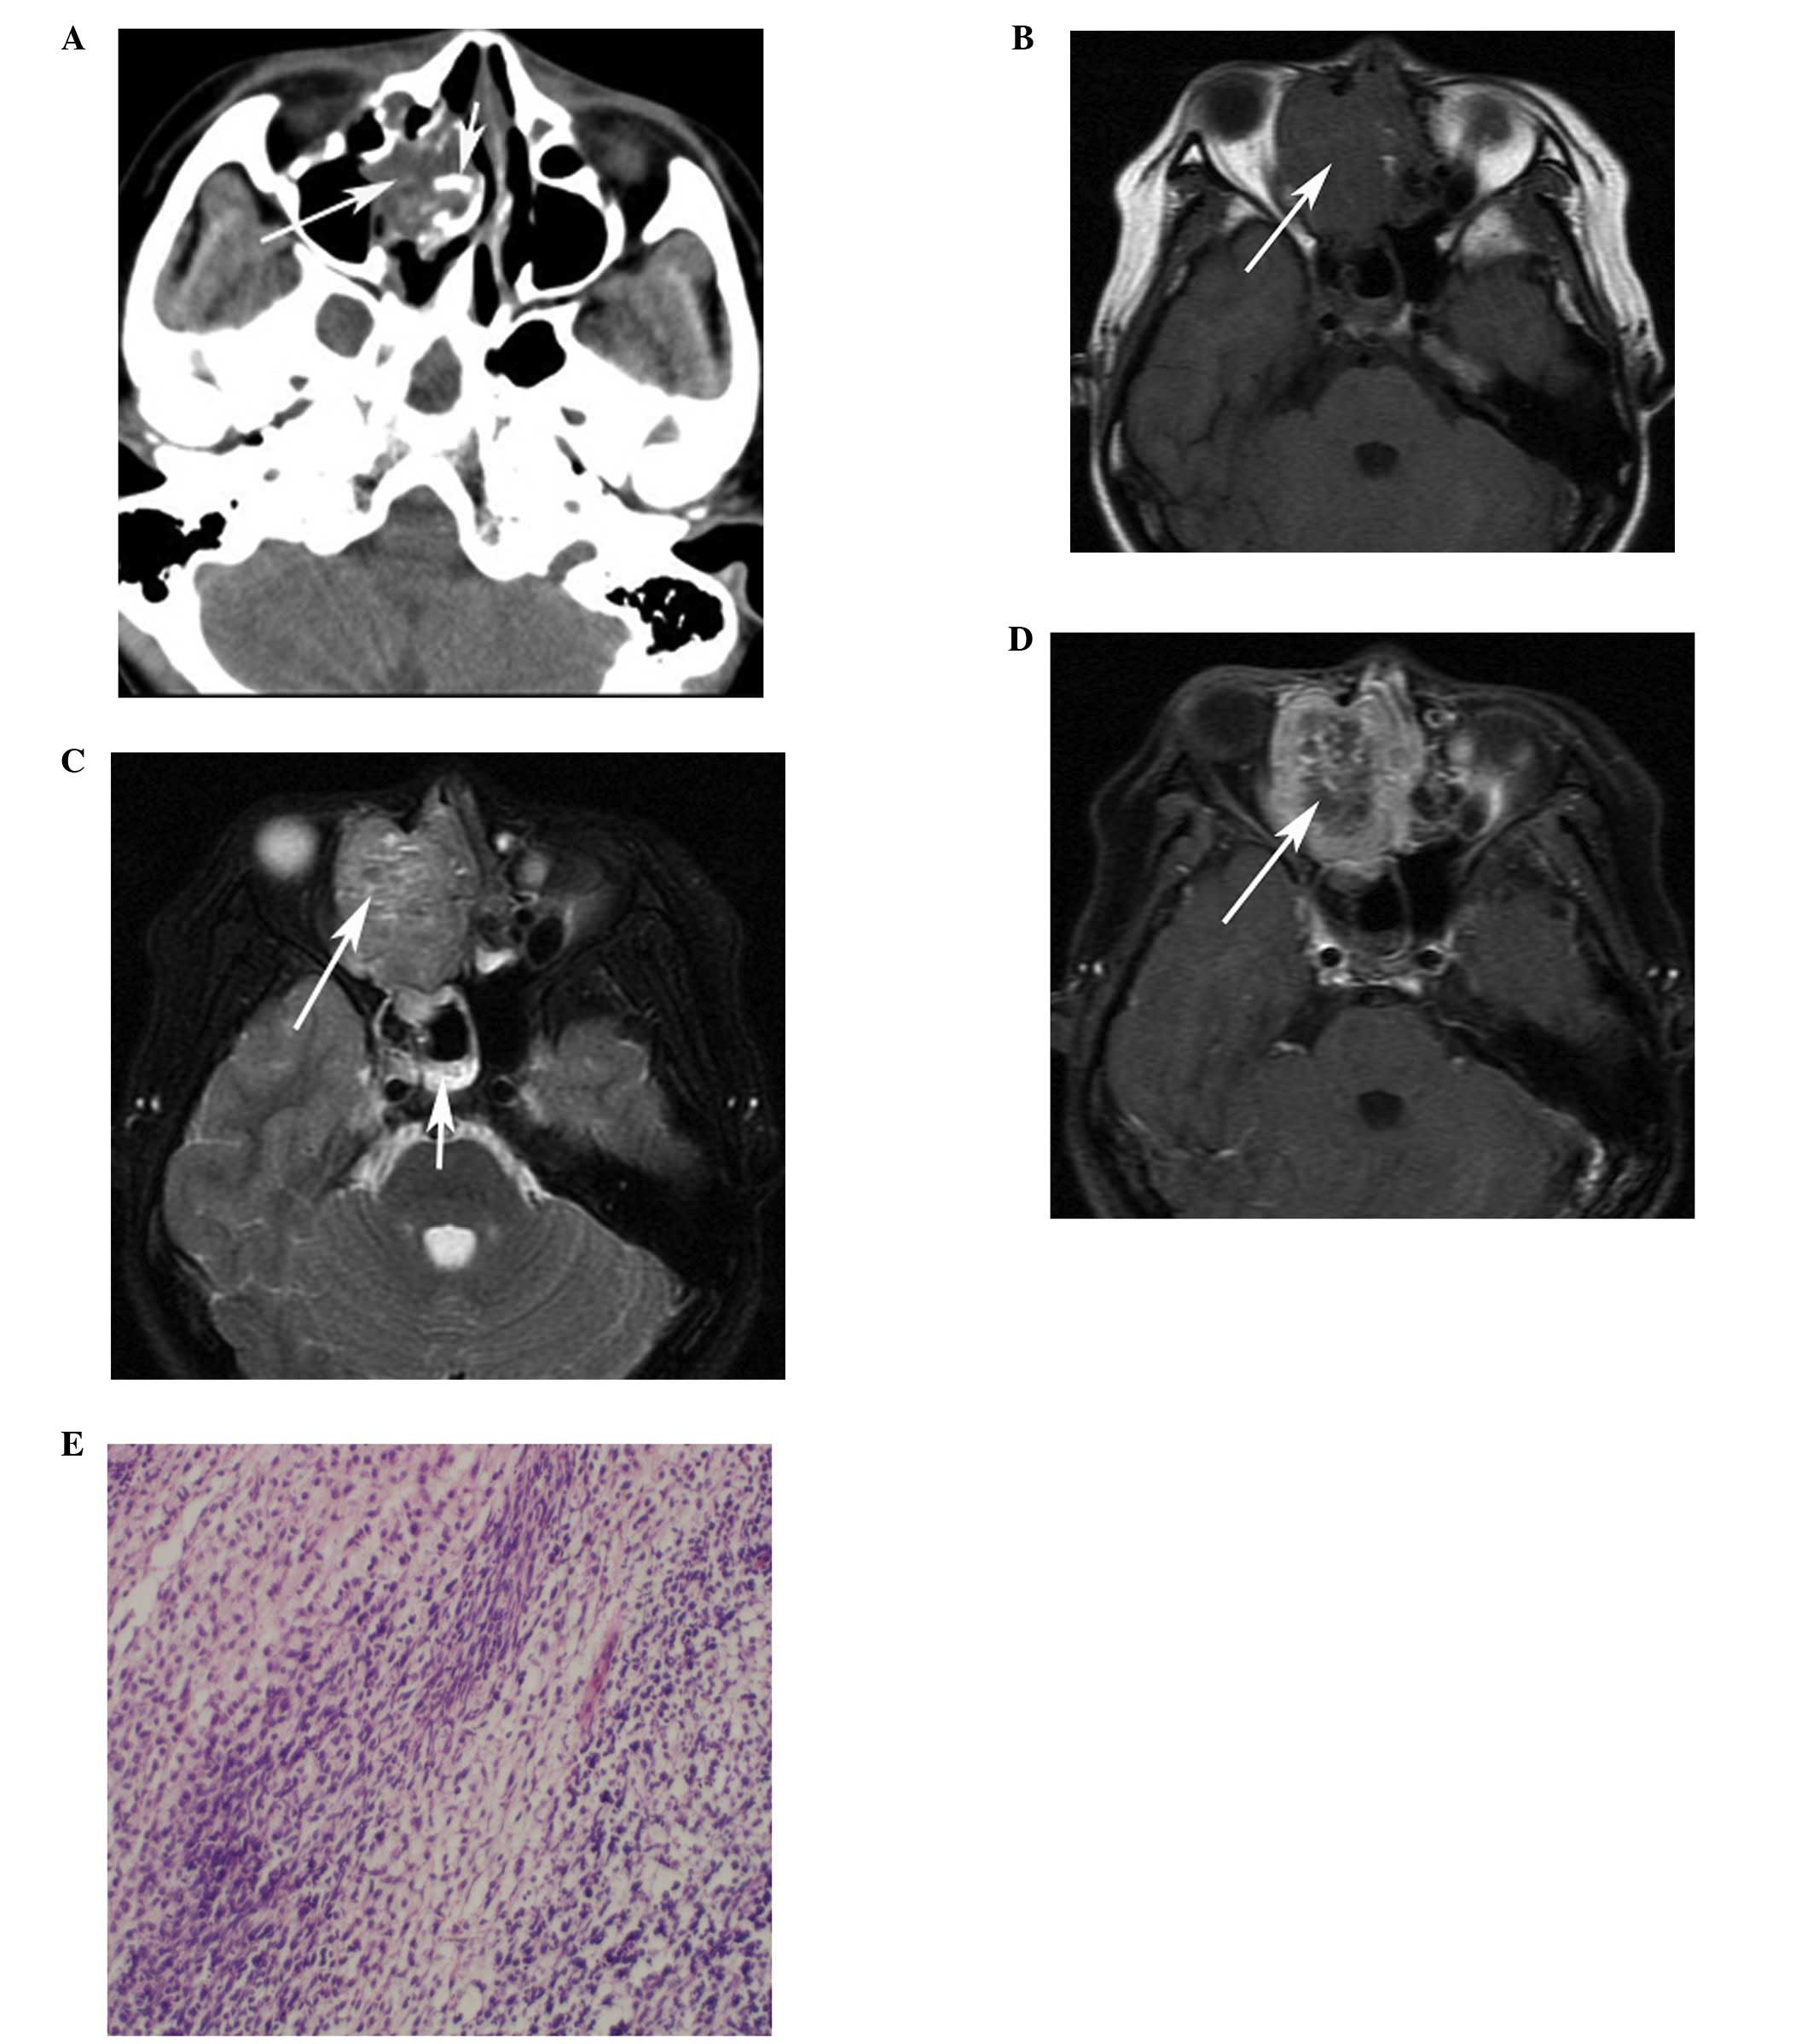

(PDF) Head And Neck Rhabdomyosarcoma: Clinical And Pathologic

www.researchgate.net

www.researchgate.net

rhabdomyosarcoma characterization pathologic

Computed Tomography And Magnetic Resonance Imaging Observations Of

www.spandidos-publications.com

www.spandidos-publications.com

rhabdomyosarcoma computed tomography magnetic imaging observations resonance neck head figure ol

An Adult Spindle Cell Rhabdomyosarcoma In The Head And Neck Region With

jmedicalcasereports.biomedcentral.com

jmedicalcasereports.biomedcentral.com

rhabdomyosarcoma spindle cell figure case survival term neck region head adult report long